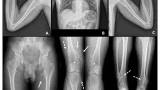

8時半に外来に降りて, 午前中は33人の患者さんの診療を行いました. 新規の患者さんが2人来られましたが, お一方は2年前から胸や背中の痛みが続いてるという患者さんでした. 今年の3月に他の病院で実施されたCTのデータをお持ちになっていたので, 確認したところ, 甲状腺に腫瘤があって, 背骨(胸椎)に骨が溶けるような病変があったので, 甲状腺癌の転移を否定する必要がありました. 至急の検査を希望されたので, 午後に造影MRIを撮ることにしました.

甲状腺癌の骨転移が疑われた患者さんのMRIが終わったので, 結果を確認したところ, 胸椎の骨が壊れて見えた部分は, 良性の骨腫瘍(血管腫)の所見であり, その存在部位からは今ある背中や胸の痛みの原因とはなりえないと判断しました.

その他に骨折の跡や骨粗鬆症もないため, 背中や胸の痛みがなぜ起きているのかは判りませんでした. 患者さんは, 精神科にも通院していたので, ひとまずは安心していただくために, 背骨やあばら骨や胸の中には痛みを生じるような病変がないことを説明しました. 引き続き, 痛みが悪化傾向なのかどうかを見て, 必要時に検査することを説明しました.